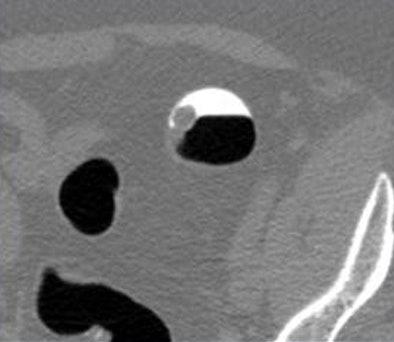

![]() |

| Above, a false-positive CAD mark highlights a submucosal lipoma. All images courtesy of Dr. Perry Pickhardt. |